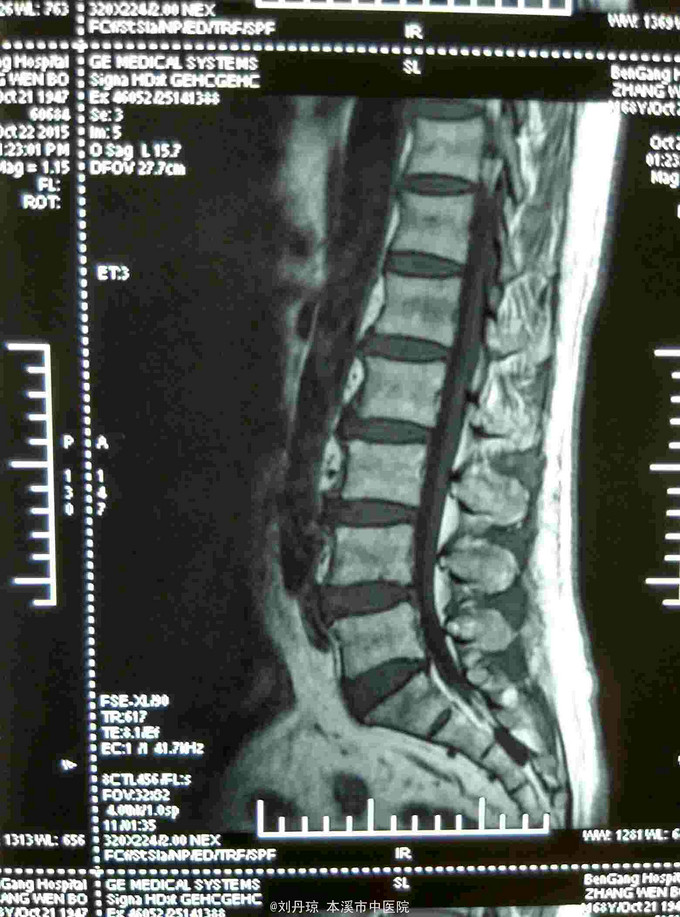

腰部间歇性钝痛伴左下肢放射痛麻木感半年。患者半年前无明显诱因感腰部间歇性钝痛伴左下肢放射痛麻木感,经多家医院治疗未见明显好转,今日来我院门诊求治,门诊医师以“ 腰椎间盘突出症、骶管囊肿 ”收入院治疗。

L4-S1棘突左侧1厘米压痛阳性,直腿抬高试验左40º右60º,加强试验左侧(阳性)右侧(阴性),腰椎功能障碍。左腿前外侧及足背外侧感觉减弱。 辅查CT: 腰椎间盘突出症、骶管囊肿

腰椎间盘突出症、骶管囊肿 治疗:骶管注射、甘露醇注射液静点、神经营养药物静点、小针刀治疗、中药熏药治疗、雷火灸治疗